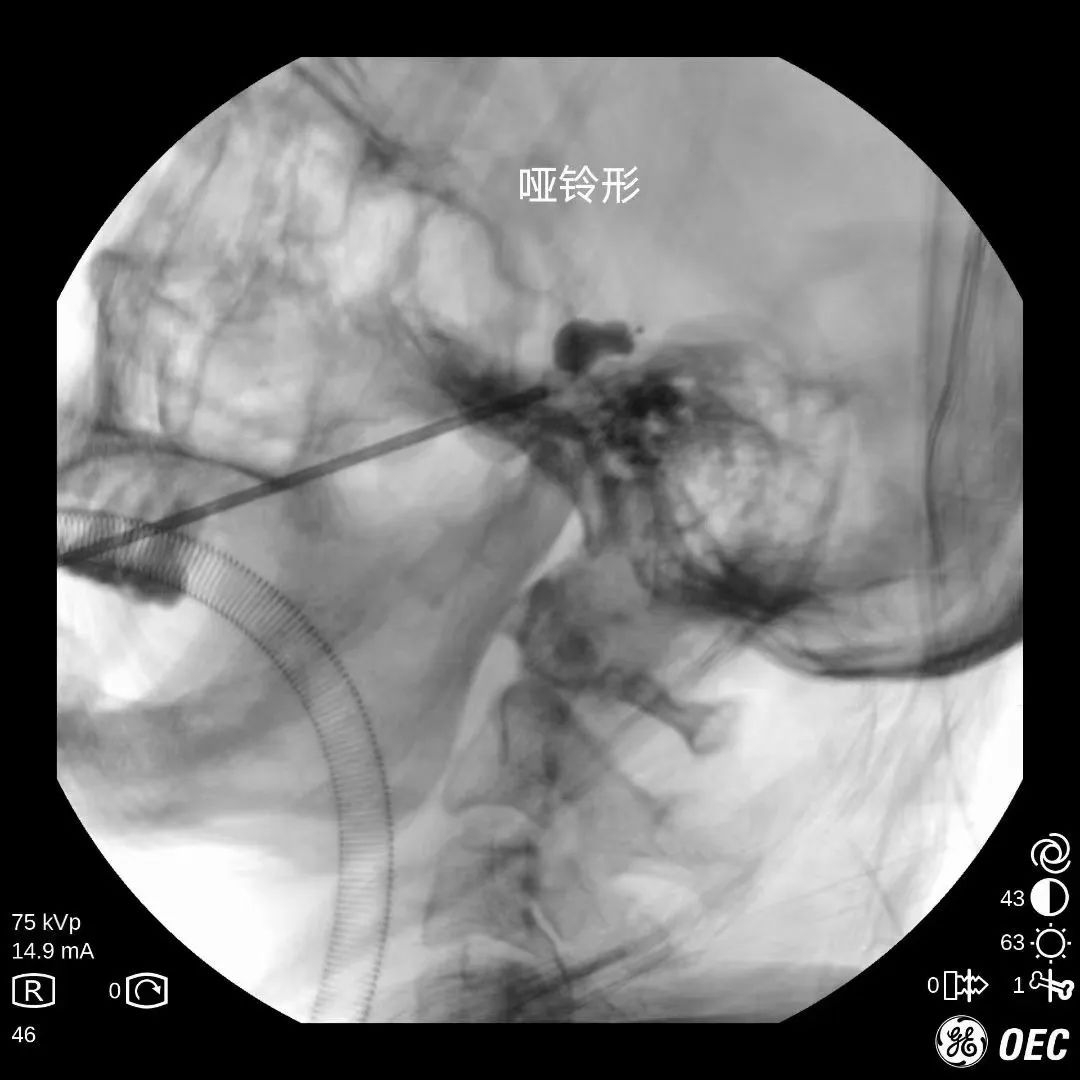

经皮穿刺三叉神经半月节球囊压迫术 :手术在C型臂及超声引导下成功穿刺至颅底孔隙,利用球囊的压力对三叉神经的关键部位进行压力治疗,使痛觉信号无法上传到大脑从而达到止痛的目的。

这种手术方法 无手术切口、安全有效、并发症少、患者恢复快, 迅速得到业界追捧,但因对术者技巧、手术器械、手术设备要求较高,开展起来有一定难度。